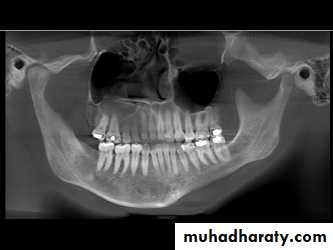

Bony abnormality, could be seen in rheumatoid arthritis or osteoarthrosis

1. OPG & Transcranial oblique lateral view.

2. Cone-beam computed tomography images (CBCT)

It is usually indicated if bony changes are anticipated like in degenerative joint diseasesRadiology

Radiology

By OPG OR Ct-Scan

It not seen in early changes

1. Erosions of the articular surfaces of the condyle (flattening) and, less commonly seen, of the mandibular fossa.

2. Sclerosis of the bone and marginal

bony proliferation (‘lipping’ or osteophytes).3. Narrowing of the radiographic joint space.

4. Bony proliferations may break away and be seen as loose bodies in the joint space.5. Subcondyle pseudocyst.